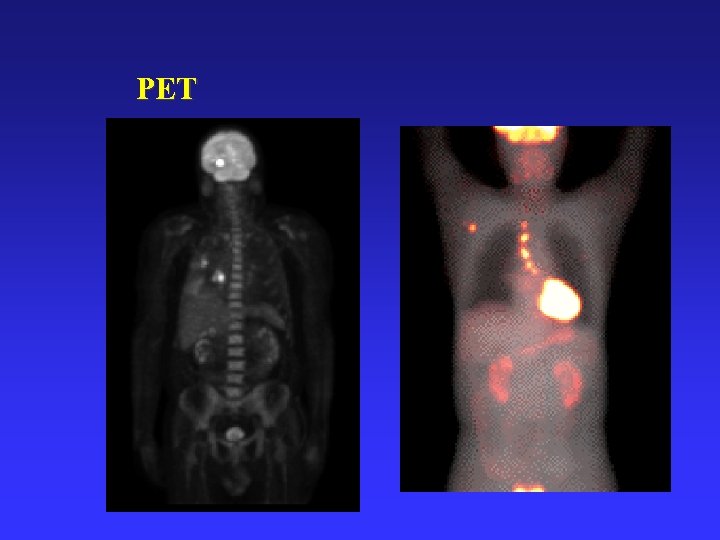

PET

1. 2 医学图像处理的发展概况 n 功能成像 20世纪 90年代 :看到功能 f. MRI:功能核磁共振成像 PET : 正电子断层成像 SPECT:单光子发射断层成像

Terms CT: computerized tomography MRI: magnetic resonance imaging PET: positron emission tomography SPECT: single photon emission tomography DSA: digital subtraction angiography PACS: picture archiving and communication system